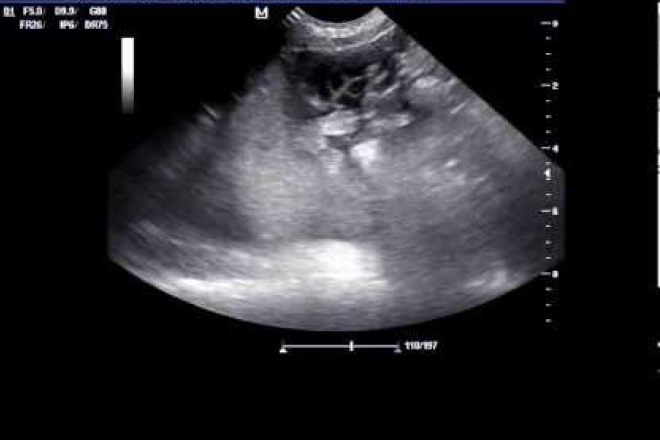

El bazo tiene ecogenicidad uniforme, es mayor que la del hígado. Tiene una textura fina y homogénea, con márgenes lisos y borde inferior afilado.